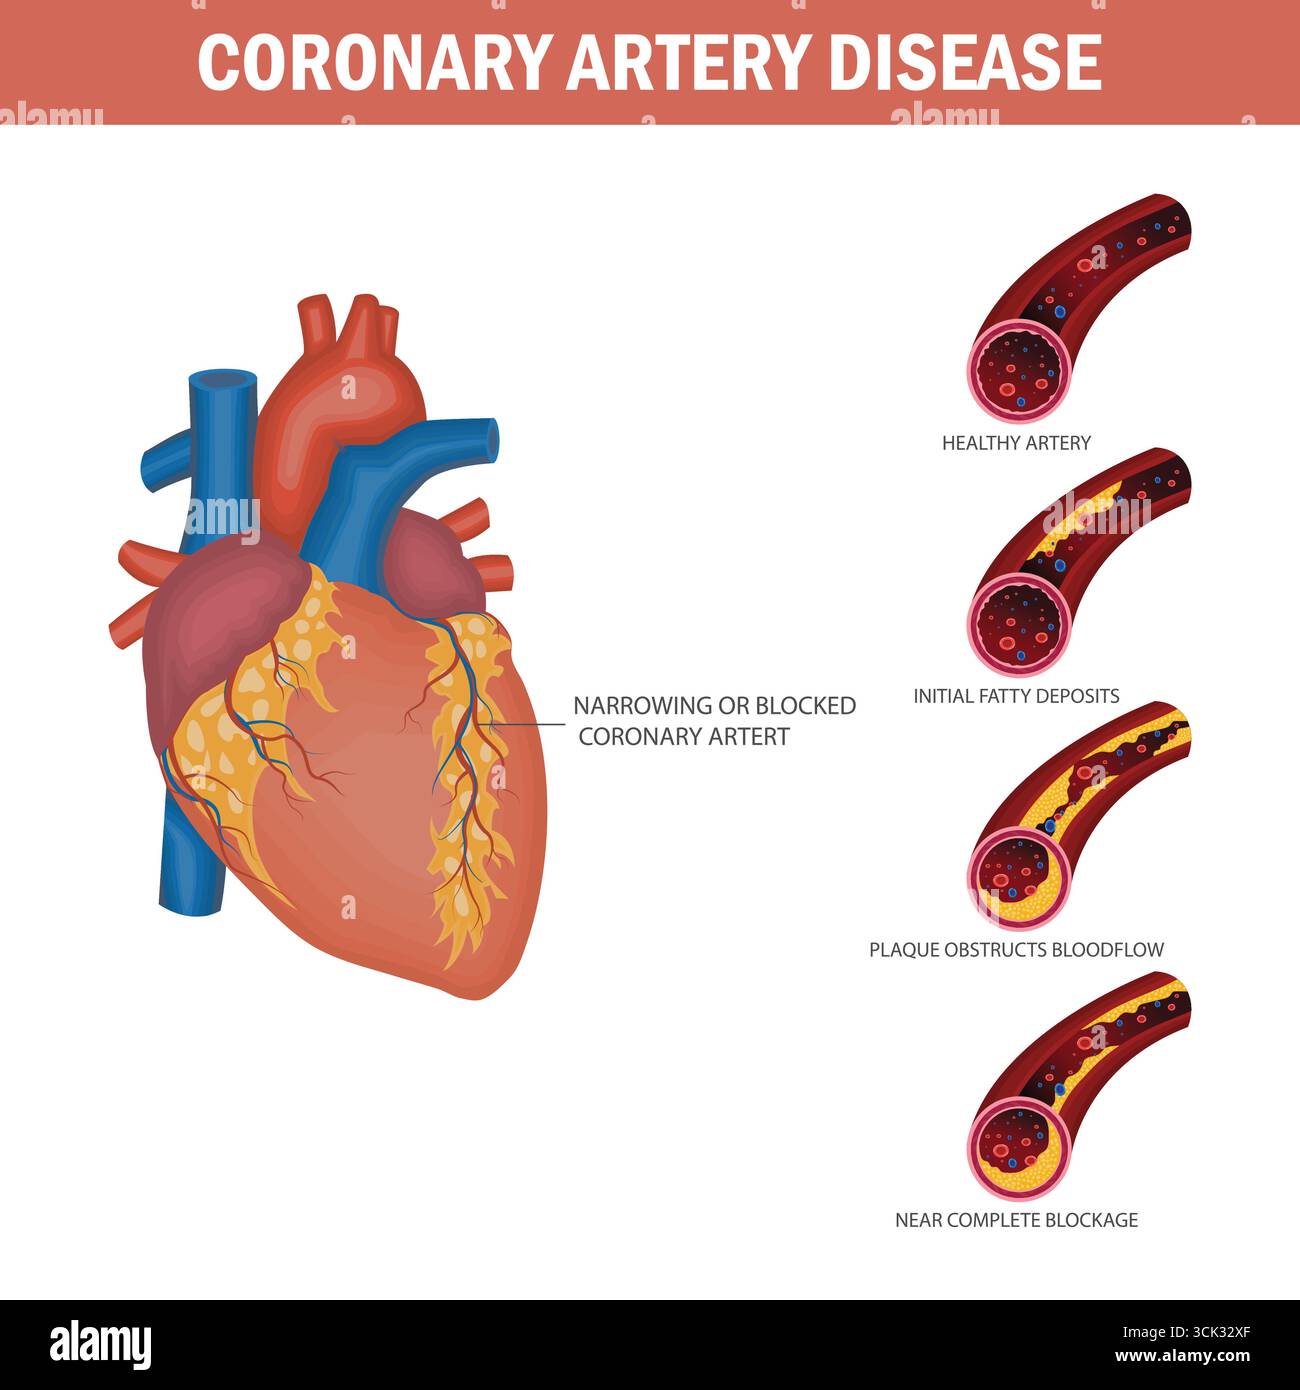

Medical illustration of coronary artery disease progression showing plaque buildup and heart artery blockage stages. Stock Vectorhttps://www.alamy.com/image-license-details/?v=1https://www.alamy.com/medical-illustration-of-coronary-artery-disease-progression-showing-plaque-buildup-and-heart-artery-blockage-stages-image700161351.html

Medical illustration of coronary artery disease progression showing plaque buildup and heart artery blockage stages. Stock Vectorhttps://www.alamy.com/image-license-details/?v=1https://www.alamy.com/medical-illustration-of-coronary-artery-disease-progression-showing-plaque-buildup-and-heart-artery-blockage-stages-image700161351.htmlRF3CK32XF–Medical illustration of coronary artery disease progression showing plaque buildup and heart artery blockage stages.

Medical illustration of coronary artery disease progression with heart anatomy and artery blockage stages. Coronary Artery Disease Progression Diagram. Stock Vectorhttps://www.alamy.com/image-license-details/?v=1https://www.alamy.com/medical-illustration-of-coronary-artery-disease-progression-with-heart-anatomy-and-artery-blockage-stages-coronary-artery-disease-progression-diagram-image700161267.html

Medical illustration of coronary artery disease progression with heart anatomy and artery blockage stages. Coronary Artery Disease Progression Diagram. Stock Vectorhttps://www.alamy.com/image-license-details/?v=1https://www.alamy.com/medical-illustration-of-coronary-artery-disease-progression-with-heart-anatomy-and-artery-blockage-stages-coronary-artery-disease-progression-diagram-image700161267.htmlRF3CK32RF–Medical illustration of coronary artery disease progression with heart anatomy and artery blockage stages. Coronary Artery Disease Progression Diagram.